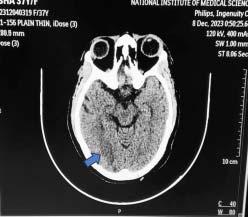

The model (Fig 1) has a classification ability of 80% (Area under ROC curve), with cut off value of 4.5 with 84.1 % sensitivity and 55% specificity. Therefore, a cut off score of 4 was chosen. A total score of <4 suggested Dengue, and >4 suggested Scrub Typhus.

This model was applied to another subset of patients, with 25 patients in each group for both Dengue and Scrub Typhus, and the results were obtained as mentioned in Table 2. The sensitivity was 72% and 48% when applied on patients who were tested positive for Dengue and Scrub Typhus respectively.

1 — ROC curve of age, hemoglobin, TLC, NLR, platelets, total

CRP, albumin and altered sensorium